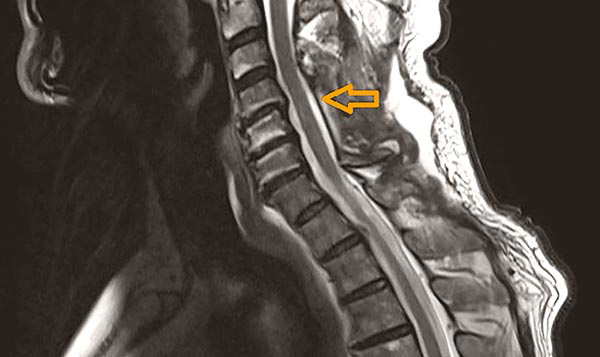

Typisch sind Schmerzen im Nacken und an den Armen sowie Missempfindungen an den Extremitäten. Die Abbildung zeigt eine Foraminalstenose also eine Einengung des Rückenmarksnerven an der Austrittsstelle. Rückenschmerzen vor allem im unteren Rücken die ins Bein ausstrahlen.

Die Symptome einer spinalen Stenose sind der der Schaufensterkrankheit nicht ganz unähnlich bei der Schaufensterkrankheit handelt es sich allerdings um eine Durchblutungsstörung. Neben der neurologischen körperlichen Untersuchung kann heutzutage durch eine MRT der HWS die Verdachtsdiagnose eines Bandscheibenschadens oder einer Spinalkanalstenose gesichert werden. Dazu gehören Schmerzen Taubheit undoder Lähmungen im.